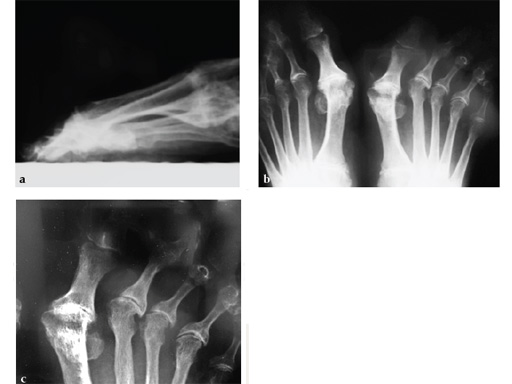

Case 2: First MTP fusion plate

A 38-year-old man presented for opinion after two attempts to fuse the big toe MTP joint. The AP view is significant for luscency at the joint line. The lateral view is notable for loosening of the hardware and malposition because of the dorsiflexion built in to the precontoured implant. Revision was planned using a 0 variable angle locking/compression hallux MTP plate.

Case provided by Michael Castro, Scottsdale, Arizona

At 10 weeks postoperatively (see Fig. 2ab) the patient had no pain with weight bearing. The lateral view demonstrates improved position of the toe using a 0angle plate.